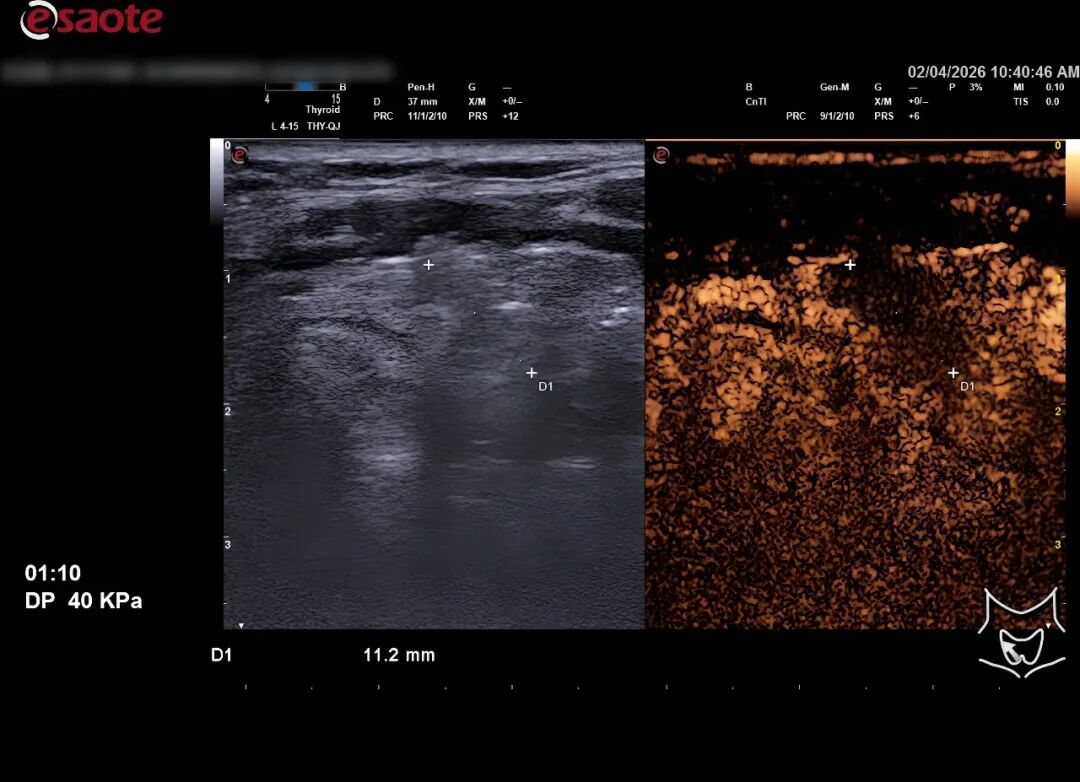

近日,云南省曲靖中心医院微创肝胆外科与超声介入科密切协作,成功为一名38岁甲状腺乳头状癌患者实施日间超声引导下甲状腺结节射频消融术。患者从入院到出院全程仅用48小时,术后恢复顺利,颈部仅留针眼大小创口,实现微创、快速、舒适康复,充分展现医院日间手术新流程、新路径的成熟与高效。

患者发现右侧甲状腺结节十余年。3月26日,经细针穿刺细胞学检查提示,右侧甲状腺叶中份结节为可疑恶性肿瘤,考虑甲状腺乳头状癌。患者担忧传统开放手术带来的颈部瘢痕、终身服药及神经损伤风险,主动要求选择创伤更小、恢复更快的射频消融治疗。医院团队精准对接患者诉求,依托成熟日间手术体系,积极探索更优诊疗路径。

针对患者病情与快速康复需求,微创肝胆外科联合超声介入科开展全面术前评估,确认患者符合射频消融适应证及日间手术标准。团队围绕安全、高效、舒适的核心目标,优化构建标准化日间手术全流程:门诊初筛→术前评估→快速入院→择期手术→严密观察→出院评估→术后随访。4月2日,手术在超声引导下顺利完成,术中精准保护周围重要结构。患者术后无声音嘶哑、出血、呼吸困难等并发症,生命体征平稳,48小时内达到出院标准,于4月3日顺利康复出院。